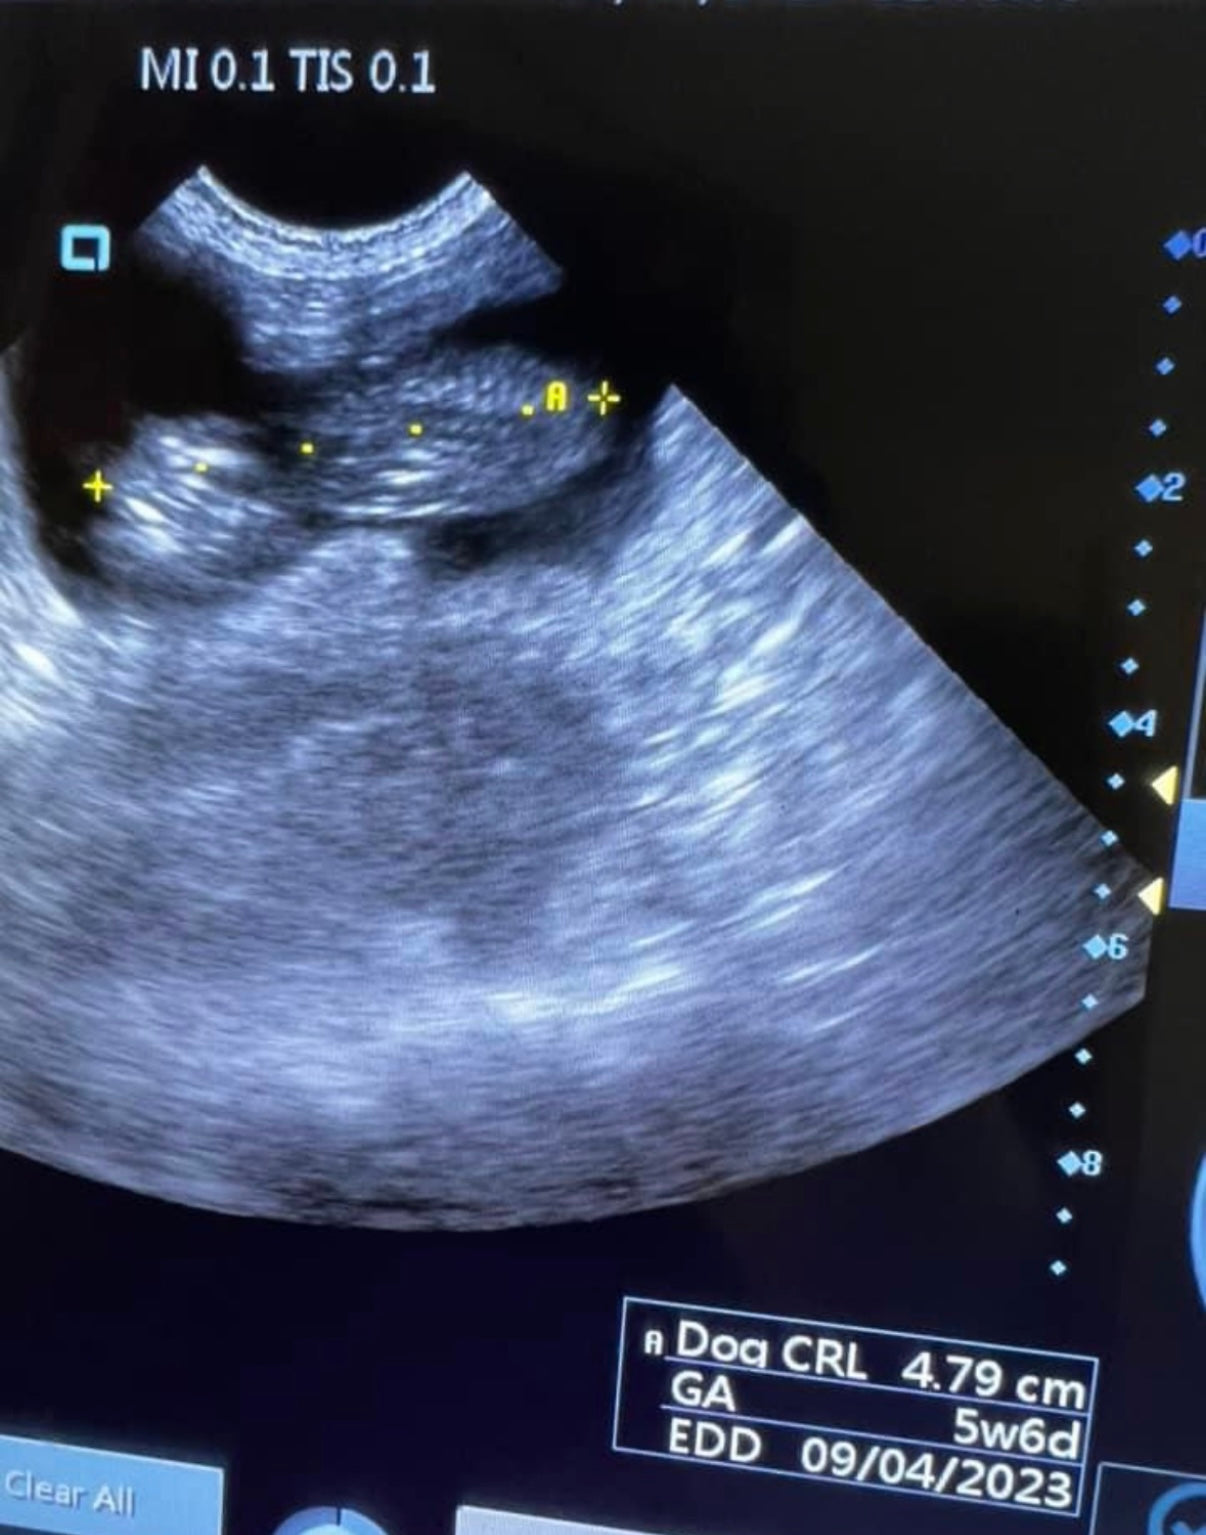

Crown-Rump Length (CRL):

This measures the size of a developing fetus from the top of its head (crown) to the base of its buttocks (rump). Although this becomes difficult to measure as the fetus grows too large for the screen.